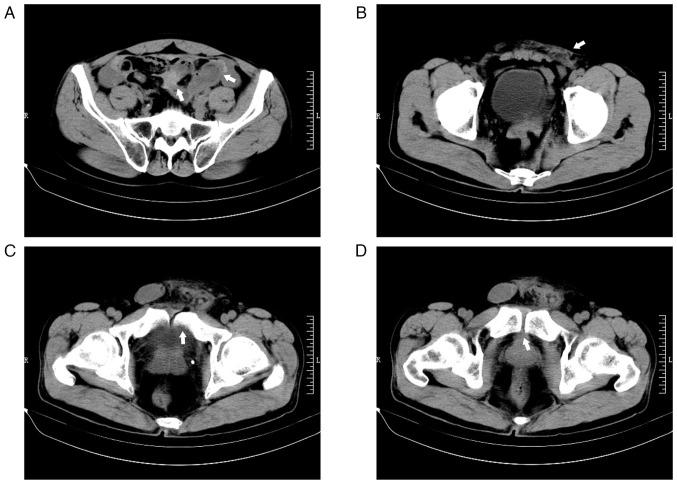

Pelvic fractures sometimes lead to injuries of the urinary bladder, which commonly present as gross hematuria, dysuria and lower abdominal pain. As a type of urinary stone, bladder stones are usually secondary to lower urinary tract obstruction, such as benign prostatic hyperplasia, urethral stricture, and neurogenic bladder. The present case report examines an unusual case of a delayed pubic fracture penetrating the bladder, which caused a secondary bladder stone. A 53-year-old man was first hospitalized at The Second Hospital of Jiaxing (Jiaxing, China) in January 2020 because of trauma-induced bleeding in the scalp and abdominal pain. The patient underwent abdominal exploration and partial bowel resection, and his condition stabilized after surgery. After discharge, the patient had regular outpatient check-ups every 2-3 weeks. However, after 3 months, in April 2020, the patient was readmitted to the hospital because of frequent urination, an urgent need for urination and dysuria. Abdominal computed tomography imaging and cystoscopy revealed a pubic fracture that had penetrated the bladder wall, accompanied by a bladder stone. Subsequently, cystolithotomy was performed, which provided significant relief of symptoms once the catheter was removed after 2 weeks. Since then, the patient has been followed up until January 2023 and had remained asymptomatic. Bladder stones caused by necrotic bone fragmentation are rare. Bladder injuries resulting from pelvic fractures can have delayed onset; therefore, clinicians should be aware of the possibility of urogenital injury in such patients. It is crucial for clinicians to comprehend the potential mechanisms involved, analyze the clinical data of patients, closely monitor their condition and implement appropriate treatment measures when necessary.

骨盆骨折有时会导致膀胱损伤,通常表现为肉眼血尿、排尿困难和下腹部疼痛。膀胱结石作为泌尿系统结石的一种,通常继发于下尿路梗阻,如良性前列腺增生、尿道狭窄和神经源性膀胱。本病例报告研究了一例罕见的耻骨骨折延迟穿透膀胱导致继发性膀胱结石的病例。一名53岁男性于2020年1月因创伤性头皮出血和腹痛首次入住嘉兴市第二医院(中国嘉兴)。患者接受了腹部探查和部分肠切除术,术后病情稳定。出院后,患者每2 - 3周进行一次定期门诊检查。然而,3个月后的2020年4月,患者因尿频、尿急和排尿困难再次入院。腹部计算机断层扫描成像和膀胱镜检查显示耻骨骨折穿透膀胱壁,并伴有膀胱结石。随后进行了膀胱切开取石术,术后2周拔除导尿管后症状明显缓解。此后,对患者进行随访直至2023年1月,患者一直无症状。由坏死骨碎片引起的膀胱结石很少见。骨盆骨折导致的膀胱损伤可能会延迟出现;因此,临床医生应意识到此类患者存在泌尿生殖系统损伤的可能性。临床医生理解其中潜在机制、分析患者临床数据、密切监测病情并在必要时采取适当治疗措施至关重要。